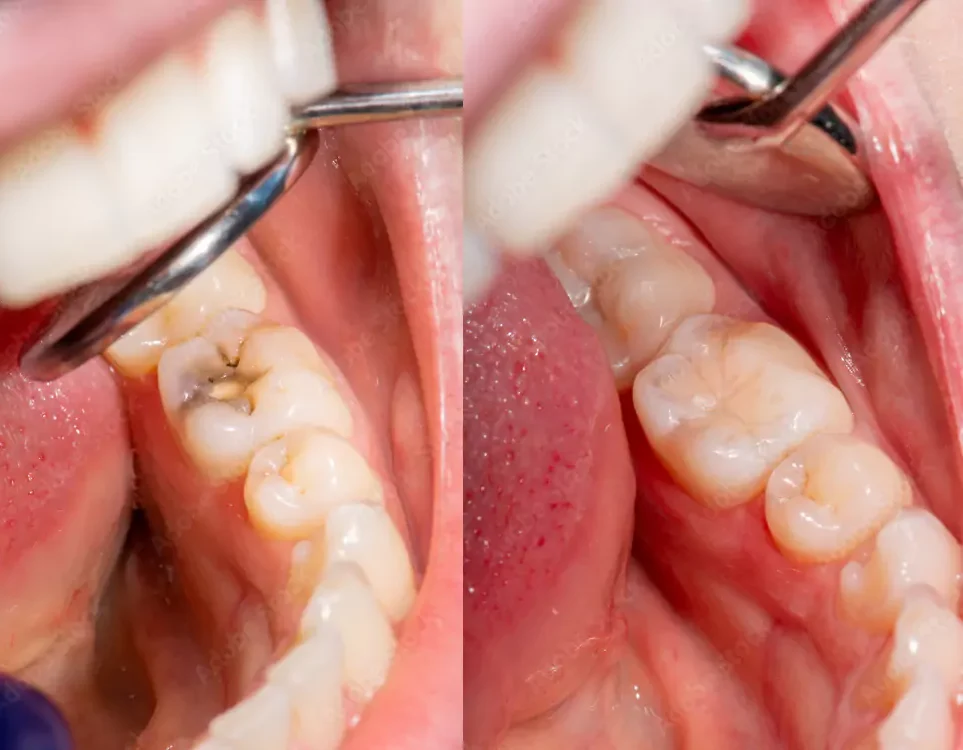

Cavities are one of the most common dental problems, but thanks to modern dentistry, they can now be treated in a way that restores both function and beauty. At Elite Dental Care and Aesthetics, we use tooth-colored fillings (composite fillings) that seamlessly blend with your natural teeth, giving you a healthy smile without compromising aesthetics.

Unlike traditional silver amalgam fillings, tooth-colored fillings are made of high-quality composite resin that matches the shade of your teeth. They not only restore strength and function but also ensure your smile remains natural and flawless.

What does the procedure involve?

Examination & Cleaning – The cavity is identified and carefully cleaned to remove decay.

Shaping the Tooth – The area is prepared for filling without unnecessary removal of healthy structure.

Filling Placement – Composite resin is applied in layers and molded to match tooth contours.

Curing & Polishing – A special light hardens the material, followed by polishing for a smooth, natural look.

Benefits of Tooth-Colored Fillings

Aesthetic Appeal – Matches your natural tooth shade, making it virtually invisible.

Strong & Durable – Provides long-lasting protection with proper care.

Minimally Invasive – Preserves more of the natural tooth compared to metal fillings.

Safe & Mercury-Free – A healthier alternative to traditional amalgam fillings.

Restores Confidence – Improves appearance while maintaining natural function.

At Elite Dental Care, we use advanced materials and techniques to ensure fillings that are durable, natural-looking, and comfortable. Whether it’s treating a new cavity or replacing old silver fillings, our team focuses on restoring your smile with precision and care.

A healthier, stronger, and more beautiful smile is just a filling away.